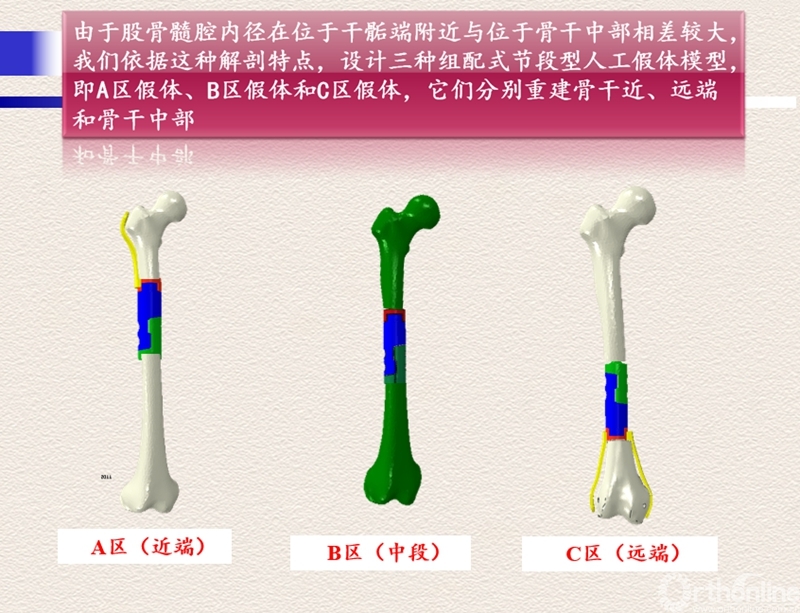

为进一步解决骨干肿瘤诊治中的难题,胡永成教授通过多年临床研究,终于设计出“骨干组配式假体”,该技术通过较小的创伤便可使患者得到好的治疗效果。除此之外,胡永成教授还根据骨干肿瘤发病部位的不同进行分区,根据不同的损伤部位可以进行个性化假体的选择,不仅可以帮助患者保留关节,患者术后还能即刻下地,大大减轻了肿瘤患者的痛苦,并提高了生存质量。

骨干组配式假体展示

分区